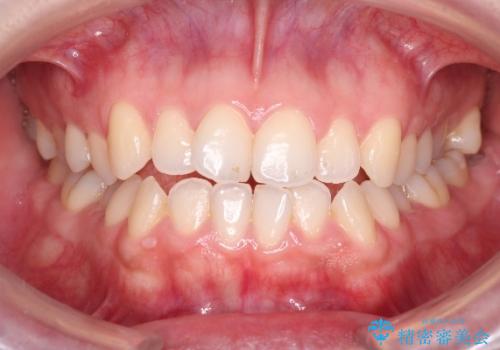

【オープンバイト】前歯のがたがたをなおしたい。

- 笑った時の前歯の見た目が気になることを主訴に来院されました。

上の歯が下の前歯を少し隠すぐらいを目指し、インビザラインにて治療を行いました。